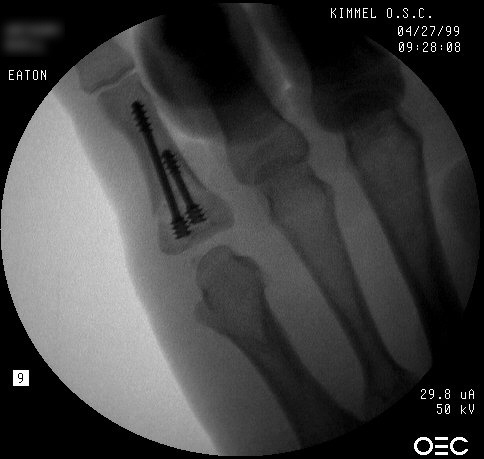

| Proximal phalanx fractures are a common problem with many treatment options. These images illustrate a technique of stabilization using intramedullary Herbert screws placed percutaneously through the base of the proximal phalanx. Provisional fixation is obtained with K wires which are replaced with Herbert screws, which simply follow the soft tissue path of the pin tract to the bone. Self tapping screws are not used in this technique, as the cutting threads catch on soft tissues. |

| One of the problems with completely displaced proximal phalanx fractures is a tendency to redisplace after temporary percutaneous pinning. This fracture was treated acutely. |